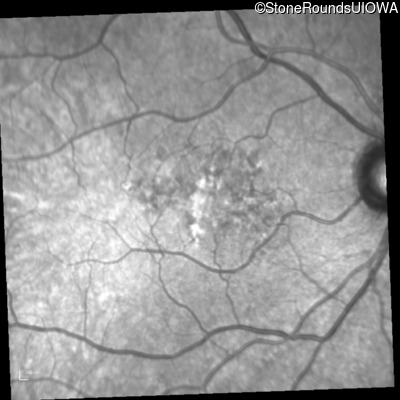

Infrared Fundus Photograph - Right - 20/20 -2

Exemplar

Infrared Fundus Photograph - Left - 20/50